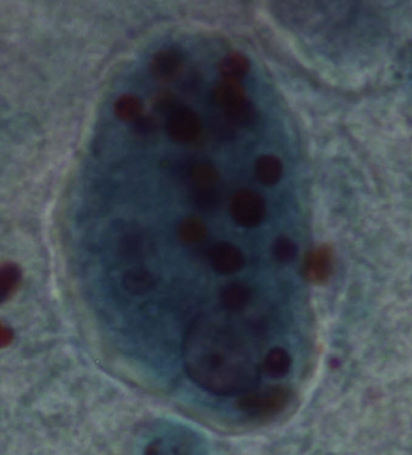

Entamoeba histolytica - Pełzak czerwonki - Trofozoit

Entamoeba histolytica - Pełzak czerwonki - Trofozoit (fagocytujący erytrocyty)